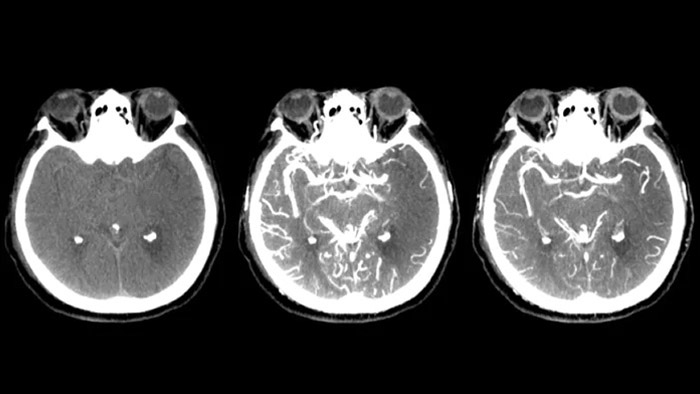

Tres SmartCT

Visualización similar a una TC

SmartCT Soft Tissue  genera una visualización de los tejidos blandos similar a la de una TC y apoya el diagnóstico del accidente cerebrovascular de tres maneras. Una exploración sin contraste ayuda a detectar los cambios isquémicos tempranos. Una exploración de fase temprana ayuda a identificar la oclusión proximal. Una exploración con contraste de fase tardía ayuda a detectar colaterales.

Ver llenado colateral

Visualización del llenado colateral

La vista dual para ver los volúmenes de TC de haz cónico de fase temprana y tardía uno al lado del otro mejora la identificación de la penumbra y permite la visualización del relleno colateral.

Control periprocedimiento de hemorragias

SmartCT soft tissue

Use las imágenes de SmartCT Soft Tissue (similar a una TC) de la suite Neurovascular para comprobar el éxito del tratamiento e identificar hemorragias.